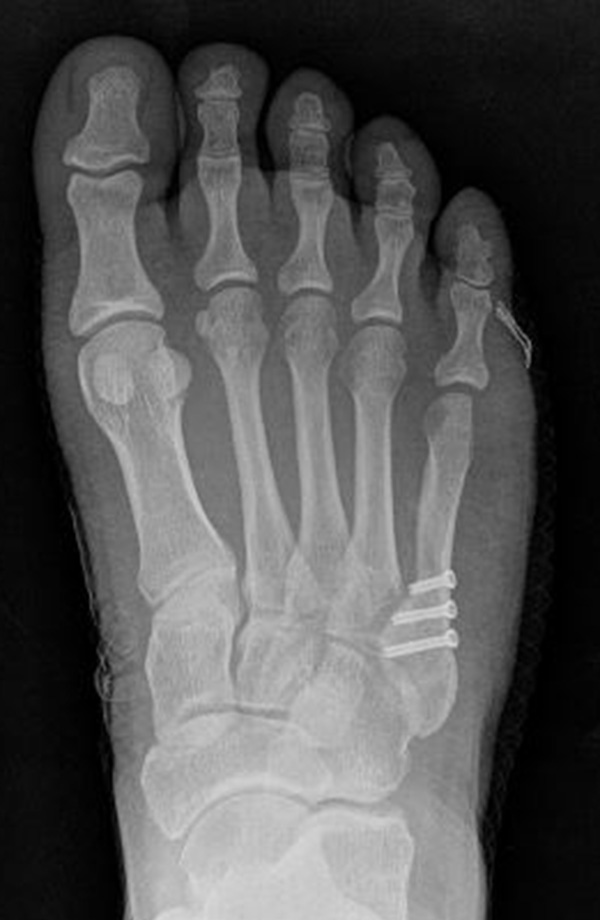

Abb. 12a: Typ III Deformität präoperativ im belasteten dp Röntgenbild.

Abb. 12b: Dorsoplantare Röntgenkontrolle nach medial schließender Osteotomie mit Schraubenosteosynthese.

Abb. 12c: Schrägaufnahme nach medial schließender Osteotomie mit Schraubenosteosynthese.

Abb. 12d: Seitliche Aufnahme nach medial schließender Osteotomie mit Schraubenosteosynthese.